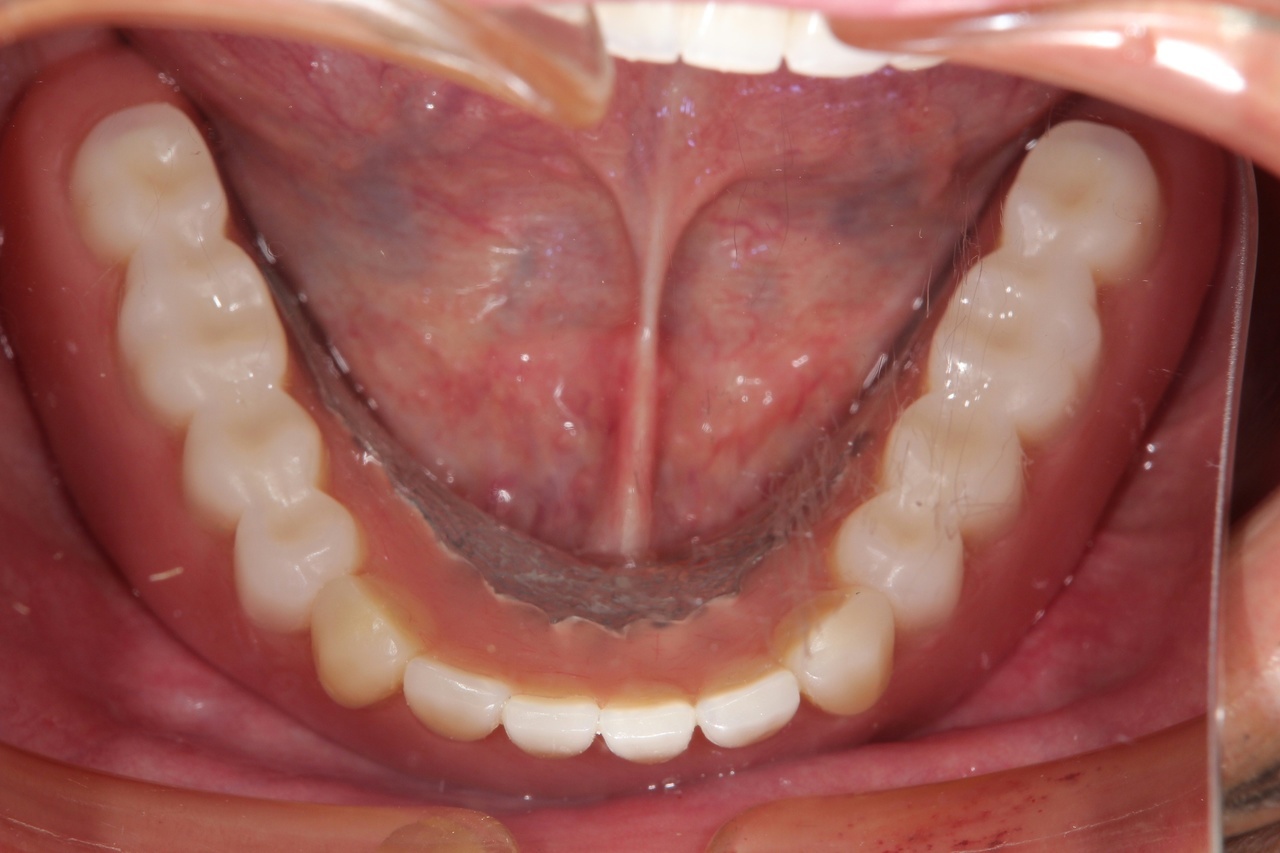

入れ歯

入れ歯装着前

入れ歯は一般的には歯を多く失った時に行う治療法で、型を取って、噛み合わせを記録して製作する取り外し可能な物です。保険で製作できますが、薄くて快適な入れ歯や、バネのないノンクラスプデンチャーは自費治療になります。

入れ歯は粘膜の上に乗せているだけなので噛むと沈み込み、土台の歯にバネの栓抜き効果が加わり、その歯が数年でダメになります。更に骨も経年と共に吸収していくので、合わない入れ歯を使用していると、更に悪化の速度が増します。

入れ歯の欠点

バネを掛けた歯は4年で90%に虫歯ができ、栓抜き効果で次々に歯が抜けてしまいます。最終的に総入れ歯になります。

入れ歯を付けている部分の顎の骨が1年間に0.5~1.0㎜ずつ痩せてしまうのです。だから、入れ歯は合わなくなるのです。